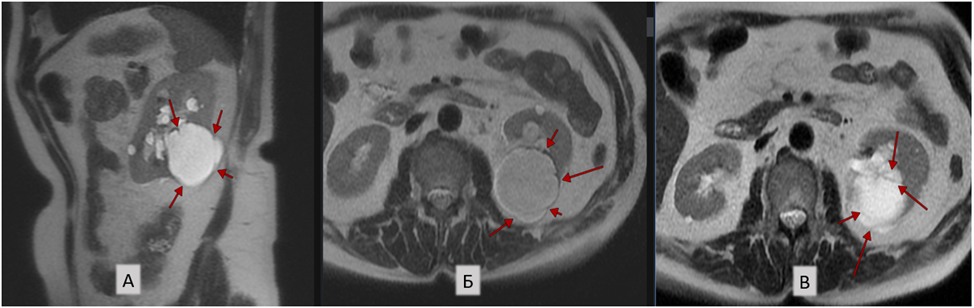

1. В нижних отделах заднего сегмента левой почки интрапаренхиматозно и субкапсулярно определяется дополнительное кистозное включение, размерами 5,2х5,6х5,5 см, с однородным жидкостным содержимым, множественными (≥4) тонкими (≤ 2 мм) перегородками, толщина стенки кисты неравномерная, несколько утолщена по внутреннему контуру кисты, максимально до 2,5 мм, с накоплением контраста стенкой на этом уровне (более характерно для IIF класса по Bosniak 2019) (рис. 1).

Рис. 1. Т2-ВИ, сагиттальная плоскость (А) и Т2-ВИ, аксиальная плоскость, разные уровни срезов (Б, В): стрелками указано кистозное включение с множественными (≥4) тонкими перегородками (авторское изображение).